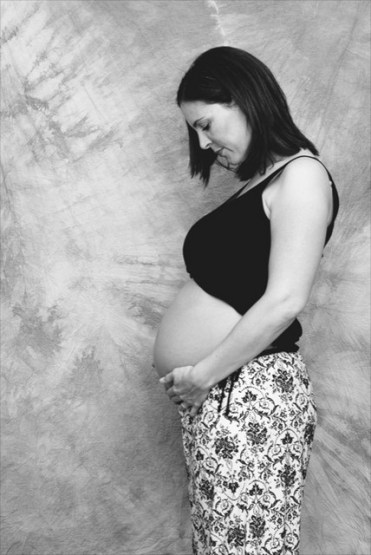

Curarsi in gravidanza è importante perché dalla salute della madre dipende la salute del bambino. Parte da questo presupposto la nuova campagna di comunicazione promossa dall’Agenzia Italiana del Farmaco (AIFA), che ha condotto un lungo lavoro di revisione della letteratura scientifica sull’uso di farmaci nelle donne prima, durante e dopo la gravidanza. Il risultato è contenuto in un sito dedicato, che raccoglie 270 schede sui principi attivi più utilizzati, 70 schede di patologia dedicate agli operatori sanitari e altrettante dedicate alle mamme. Si tratta di un sito, quindi, che parla agli specialisti del settore ma anche alle donne, informando sui rischi e sui benefici dell’assunzione dei farmaci in un periodo cosi delicato e suggerendo, per le patologie prese in considerazione, il trattamento ad oggi più sicuro.

Proprio per questo le donne non devono rinunciare a curarsi, per non esporre se stesse e il proprio bambino a possibili rischi legati alla mancanza piuttosto che alla presenza di cure. L’importante è assumere farmaci, e qualsiasi altro tipo di prodotto, in gravidanza con atteggiamento responsabile e secondo le indicazioni del medico, evitando rimedi fai da te. “Il sito è molto interessante. La sezione dedicata ai medici – spiega Salvo Di Grazia, medico ginecologo e divulgatore scientifico – fornisce, per le patologie più importanti, l’elenco dei farmaci più sicuri, analizzando il rapporto rischio/beneficio per ognuno e fornendo una bibliografia e i giusti riferimenti alla letteratura scientifica. Anche per le mamme è uno strumento utile. Spesso la donna in gravidanza è bombardata dai consigli delle amiche e viene sopraffatta dalla confusione. La paura di assumere farmaci in gravidanza è giustificata ma, quando si rendono necessari, bisogna informarsi da fonti attendibili, primi fra tutti i medici, e non affidarsi al sentito dire”.

Questi, quindi, i messaggi fondamentali che si vuole far arrivare alle donne in gravidanza attraverso questa iniziativa: curarsi in gravidanza è possibile e consigliato, perché dalla salute della mamma dipende anche la salute del bambino, ma bisogna farlo con responsabilità e secondo il consiglio di medici ed esperti. Anche nel caso di patologie croniche, che necessitano cure farmacologiche costanti, è possibile portare a termine con successo una gravidanza, pianificando prima con i propri medici i trattamenti più opportuni da seguire. E infine, ricordarlo ancora non è mai superfluo, informiamoci in modo corretto e da fonti attendibili.